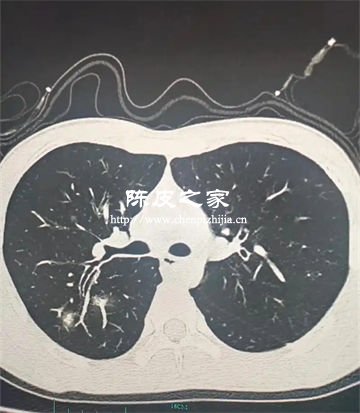

支原體肺炎由肺炎支原體引起,該病原體無細胞壁,對β-內酰胺類抗生素天然耐藥。陳皮中的活性成分尚未被證實能直接殺滅或抑制肺炎支原體,無法替代抗菌藥物治療。